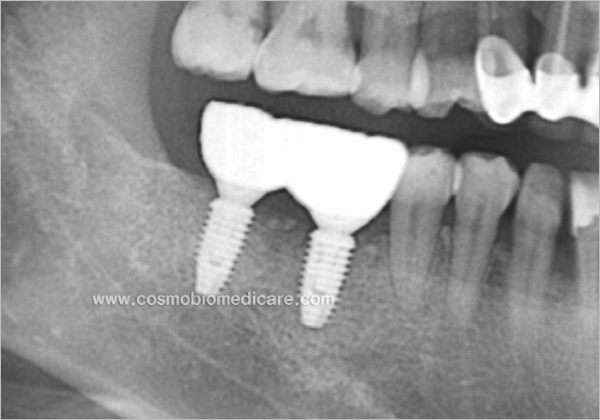

Clinical Cases

• Case1

• Case2

• Case3

• Case4

• Case5

• Case6

• Case7

• Case8

• Case9

• Case10